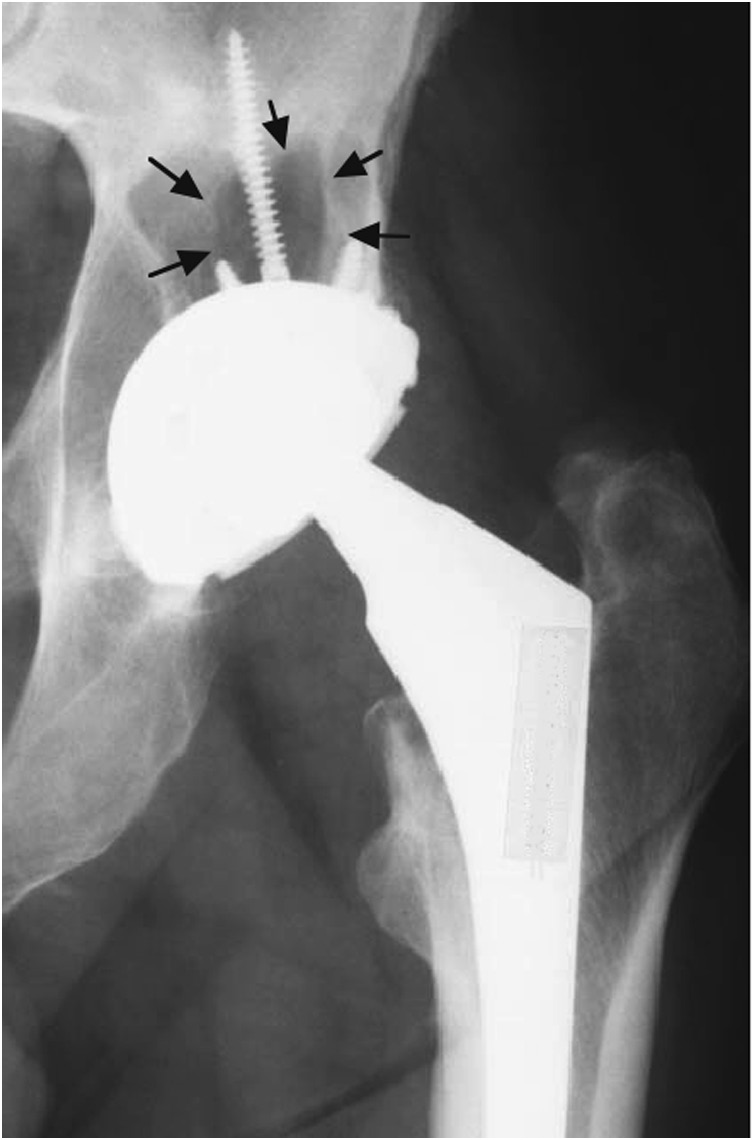

中的X光片显示了骨盆内一个骨溶解病灶,位于历史性的γ射线灭菌髋臼部件上方。

第一代模块化髋臼部件设计(Harris‐Gallante,捷迈,印第安纳州华沙)中通过X光片估算的线性和体积磨损率的分布。这些图表显示了磨损率随植入时间延长而降低的趋势。结果基于仅前后位X光片(二维)分析,以及前后位和侧位X光片联合分析(三维)进行比较。数据由芝加哥大学伊利诺伊州芝加哥市J. 马丁内尔医生提供。